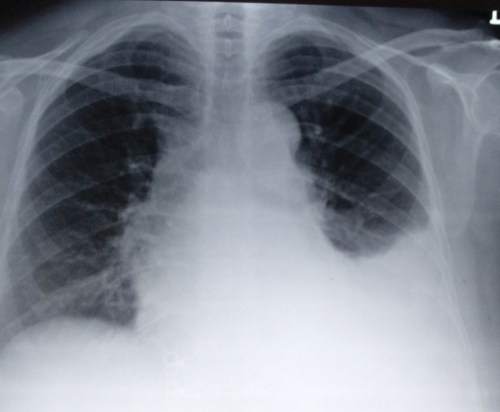

This patient came to my lab for the Echocardiogram .The echo window was poor , It showed a structurally normal heart and there was no pericardial effusion. I suspected something systemically wrong in this patient and asked for a X ray chest .

Subsequent scrutiny of this patient revealed she had moderate left tuberculous effusion. ECG changes are attributed to this. We know pericardial disease can cause ECG changes that mimic ACS. While pericarditis can elevate the ST segment. Can pleuritis without effusion cause ECG changes. What is the demarcation point between pleural from pericardial surface ?

I think X-ray chest is least used modality in a coronary care unit for various reasons . Still ,the utility of which can never be undermined and should be used diligently .